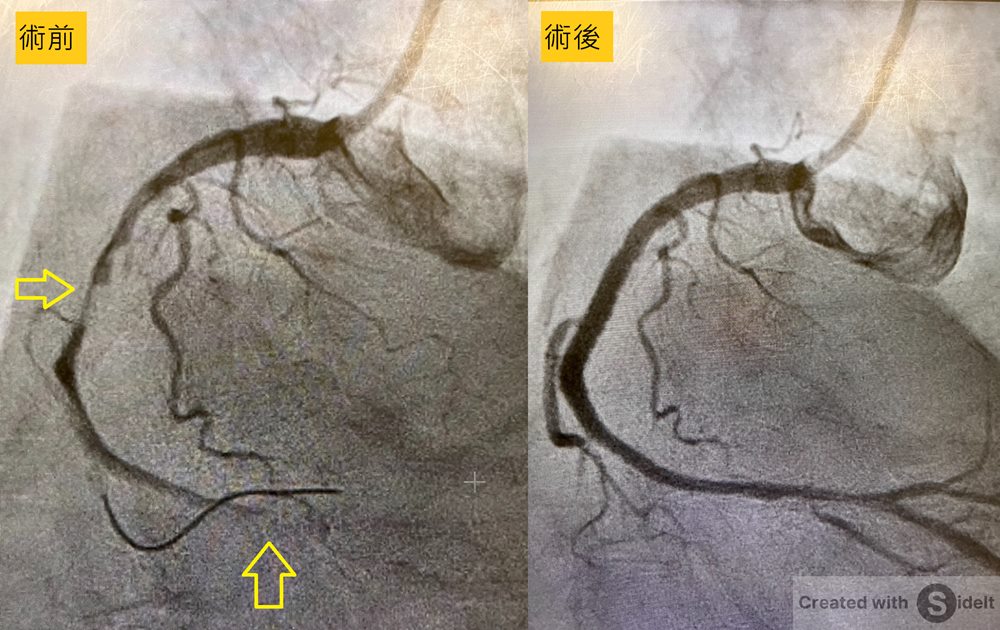

台中市一名70歲男子日前突然感到胸悶疼痛、冒冷汗,緊急到醫院就診,被醫生認為是心肌梗塞,馬上安排心導管檢查,發現他的右冠狀動脈中段處遭血栓近乎完全堵塞!

由於這名老翁吸菸長達40年以上,且有三高及心房顫動病史,使得他更容易發生此類心臟事件。醫生馬上幫老翁的右冠狀動脈中段上打通並放置支架。幸好,手術順利完成,老伯伯的生命危機解除,目前已出院並定期回診追蹤。